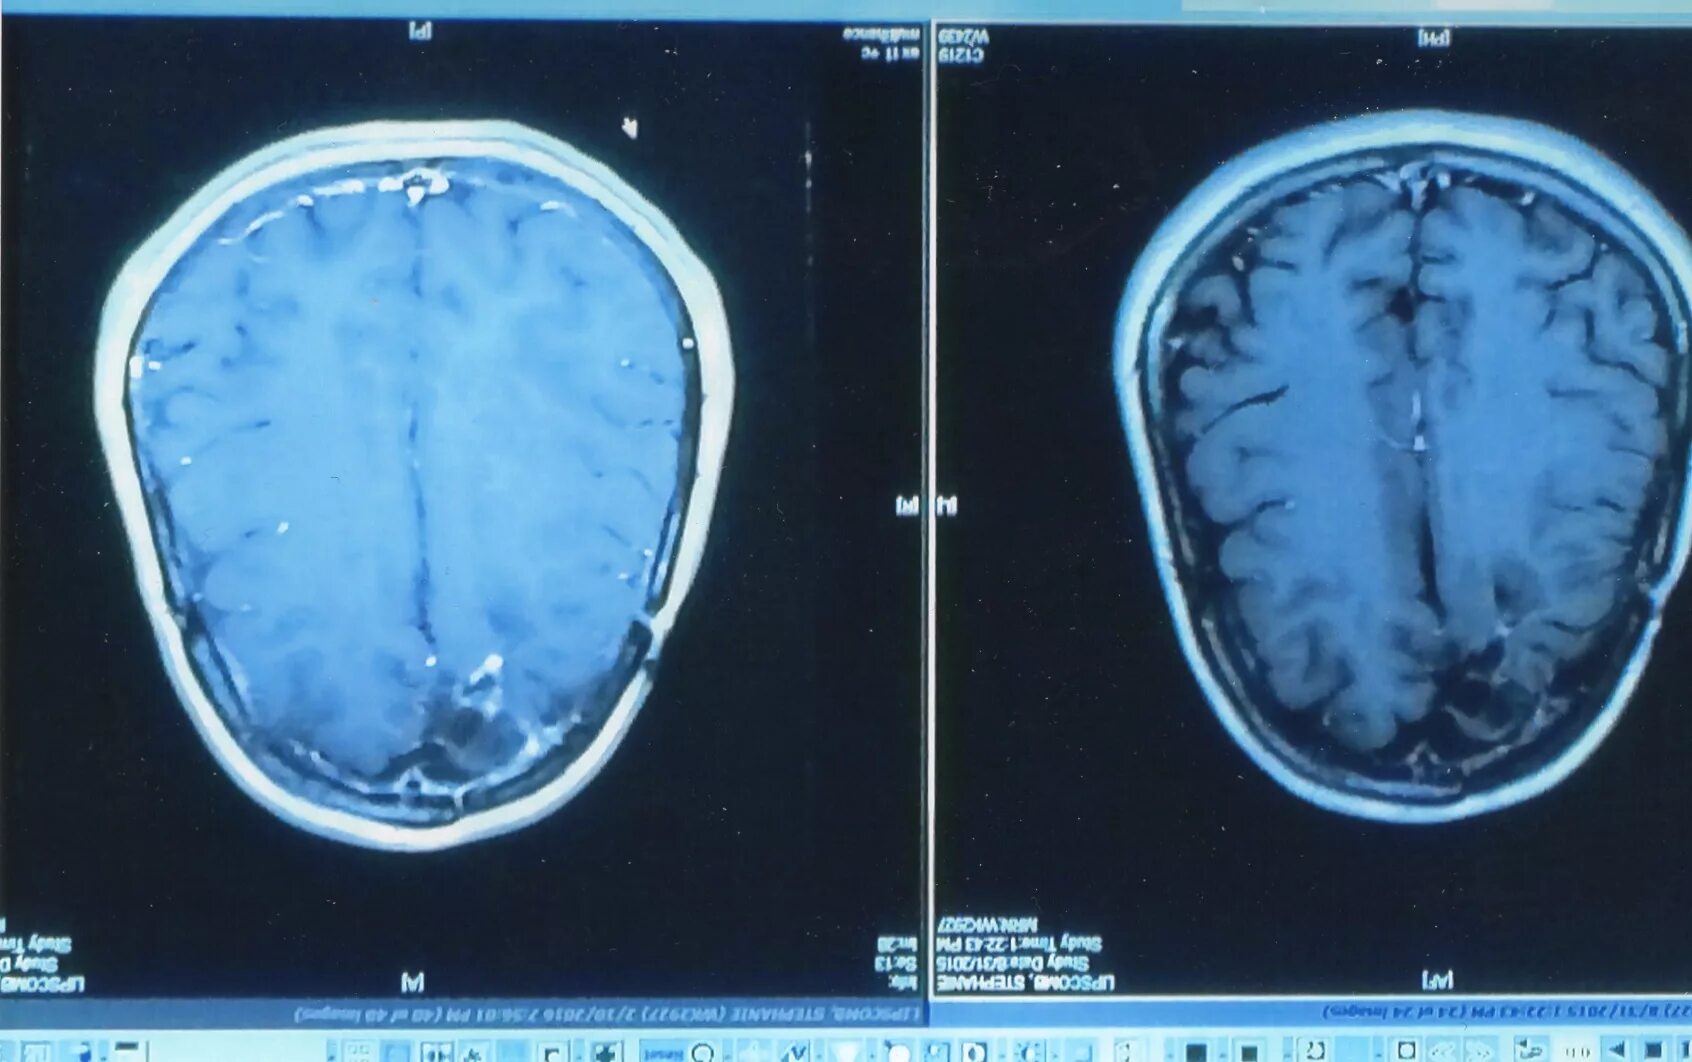

Отек мозга ишемия